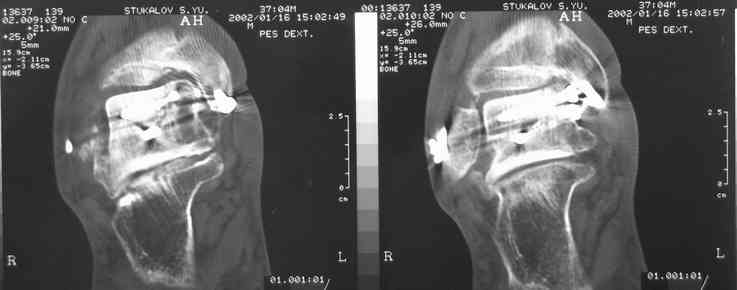

Случай с множественным оскольчатым переломом тарана оперированный из двойного доступа.

Через 2 мес.:

Через 8 мес.:

Через 14 мес.:

И второй случай из недавней ташкентской практики, (извините за качество ренгенограммы и только в одной проекции) случай падения с высоты (кстати моего друга - известного киноактера) - открытый

смещенный перелом тарана, с переломом переднего края дистального эпиметафиза большеберцовой кости.

При поступлении в приемной сделана первичная обработка с ушиванием открытой латеральной раны и вытяжением за пятку.

Из-за отсутствия времени пришлось оперировать на второе утро, из материала, что имеем на месте, фиксирован двумя шурупами, а третий-это контур сломанного жойстика в 4 мм. На дистальный медиальный конец тибиа antiglide 3.5 мм пластина. Через пару дней выписан и несмотря на предупреждение, самостоятельно начал нагрузку в 4 недели, время не ждет, снимается в боевике в Росийской Федерации.

На ренгенограмме не уловил многоскольчатость тарана, чтобы доказать, конечно, можно было исследовать на КТ, потом КТ дает ориентацию фрагментов.

Два фрагмента суставной поверхности тарана можно восстановить боковой компрессией шурупами и дополнительно костная пластика.

(кстати, на нашем случае была применена костная пластика-allograft crouton для заполнения дефектов)